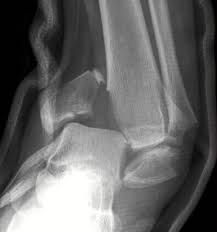

Ankle Fractures Trauma Orthobullets

Ankle Fractures Trauma Orthobullets from upload.orthobullets.com

L4 or l5 transverse process fractures. Transverse process fracture is a rare and stable fracture of the spine. Dissection or occlusion of the vertebral artery has been reported in 88% of transverse process fractures that extend to transverse foramen. It occurs as a result of sudden and extreme trauma. Fractures at the level of the spinal cord (above l1/2 ish) are much more vulnerable to neurologic injury than injuries below and require a more urgent treatment. However, since tpfs can also occur due to repetitive loading, this underreporting may be quite significant(8). Vertebral angiography, performed in eight patients with fractures involving the transverse foramen, showed dissection or occlusion of the vertebral artery in seven (88%) instances. Care guide for transverse process fracture.